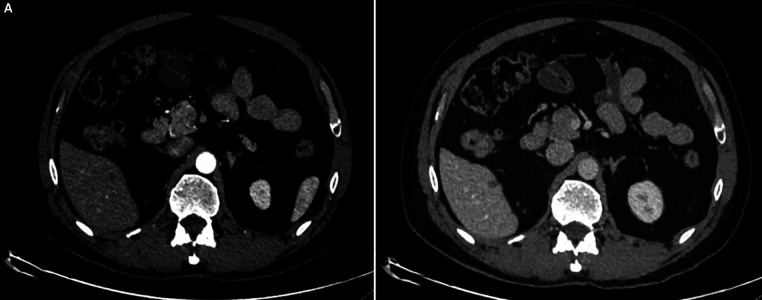

贝伐单抗和阿特唑单抗联合治疗是治疗晚期肝细胞癌(HCC)的首选组合之一,然而单药治疗的证据并不令人信服。我们报告了一个50多岁的男性HCC合并脊柱转移的病例,他对联合治疗有很好的反应。然而,他继发于贝伐单抗后出现了严重的蛋白尿和高血压,在18个周期后不得不停药。在做出明智的决定后,继续使用阿特唑单抗,患者表现出持续的反应。迄今为止,他在停用贝伐单抗后又接受了16个额外周期的atezolizumab单药治疗,并继续显示出持续的反应,目前无进展生存期超过30个月。如我们的报告所述,atezolizumab作为长期单药治疗的有效性是初始联合治疗的残余效应,还是HCC对单独免疫治疗具有内在反应,需要进行前瞻性评估。如何引用本文:Naviwala MSS, Shoaib D, Khan WA等。晚期肝细胞癌停止使用VEGF抑制剂后免疫治疗完全缓解:1例报告。中华肝病与胃肠病杂志;2009;14(2):246-250。

Bevacizumab and atezolizumab combination is one of the preferred combinations for managing advanced hepatocellular carcinoma (HCC), while the evidence on monotherapy with either agent is not convincing. We present a case of a man in his 50s diagnosed with HCC with spinal metastases who showed a good response to combination therapy. However, he developed severe proteinuria and hypertension secondary to bevacizumab, which had to be discontinued after 18 cycles. After an informed decision, atezolizumab was continued and the patient showed a sustained response. Till date, he has received 16 additional cycles of atezolizumab monotherapy after discontinuation of bevacizumab and continues to show a persistent response, with a progression-free survival of over 30 months now. It needs to be prospectively evaluated if atezolizumab's effectiveness as monotherapy for extended periods, as in our report, is a residual effect of initial combination therapy or if HCC is intrinsically responsive to immunotherapy alone.